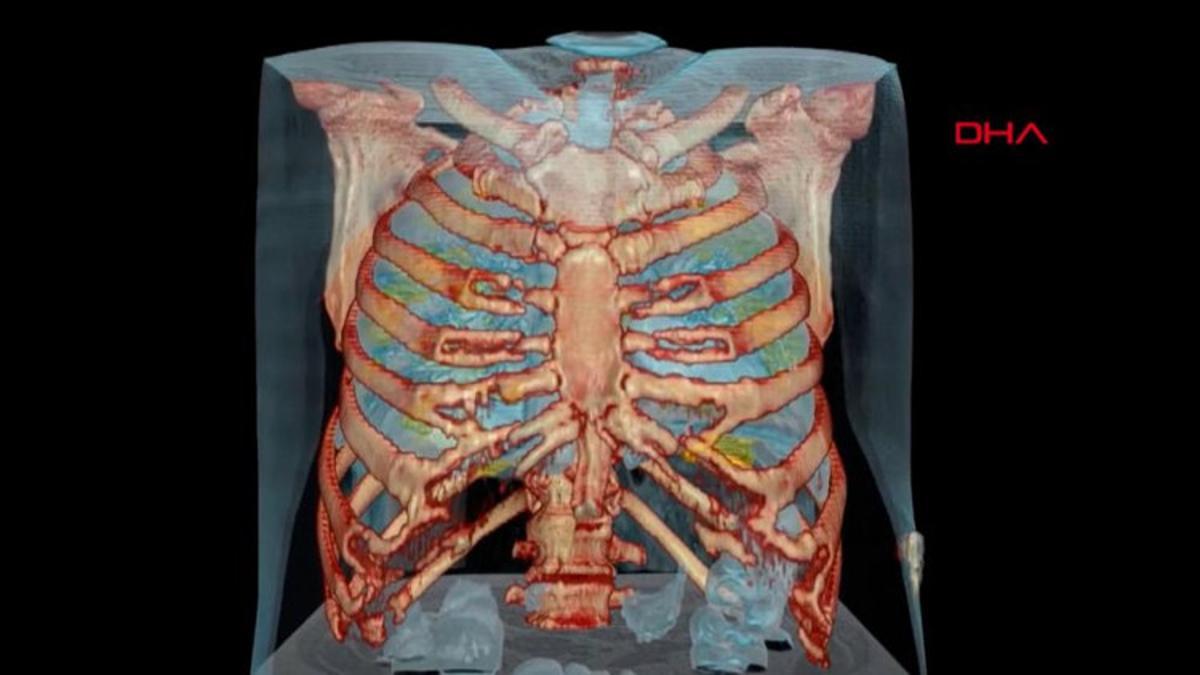

Iste Koronaviruslu Akcigerin 3d Goruntusu En Son Haberler

www.hurriyet.com.tr